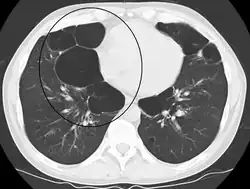

Asymmetric bullous emphysema

An axial CT image showing bullous emphysema of the lungs. There are larger air pockets on the right than left.

Bullous emphysema is a condition seen in patients with chronic obstructive pulmonary disease (COPD). The units making up the substructure of the lung (alveoli) become permanently enlarged due to the destruction of their walls. This leads to hyperinflation of the alveoli and, thus, the lungs. When this occurs asymmetrically, one lung can be larger than the other.[23] A severe variant of this condition is called giant bullous emphysema. On chest x-ray, one lung will be significantly more inflated than the other, causing a mediastinal shift. Bullous emphysema's radiographic appearance on x-ray mimics a tension pneumothorax. This presents a medical challenge as these diseases are treated differently despite appearing similarly on x-ray.[24][25]